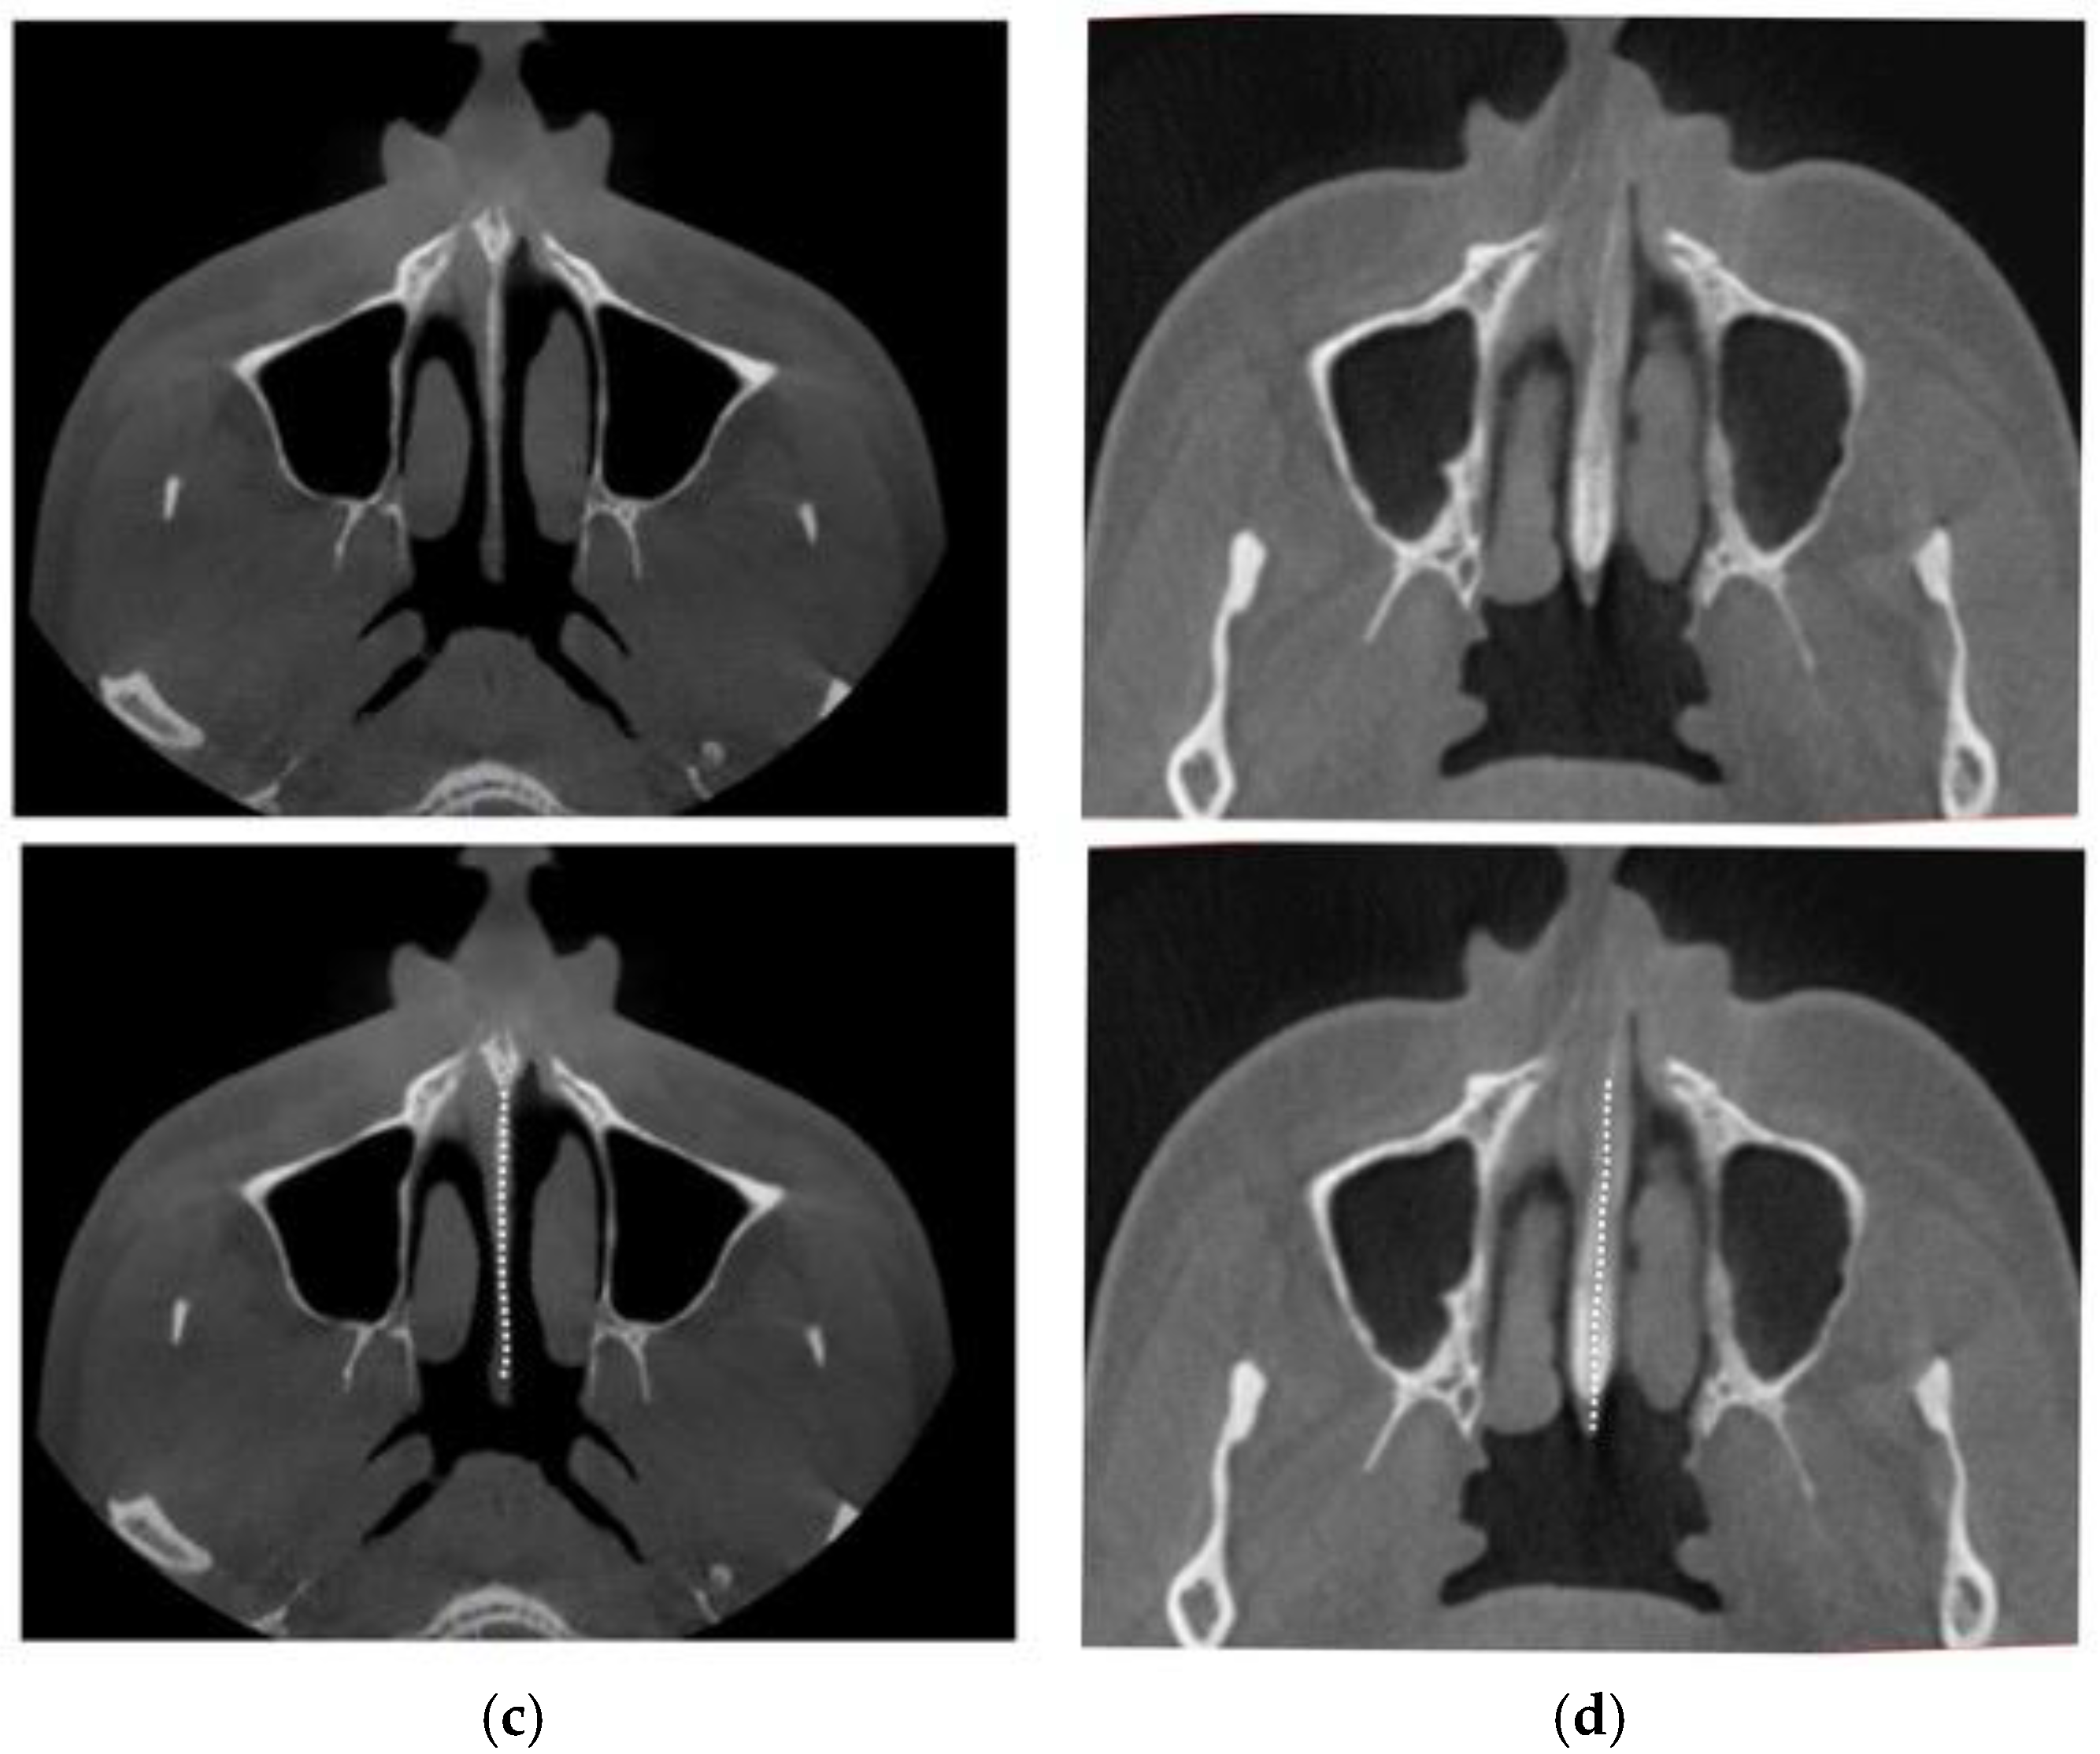

2.4. Case A: Blind Midpalatal Piezocorticotomy with MARPE Expansion

2.5. Case B: Guide-Assisted Midpalatal Piezocorticotomy

2.6. Case C: Bilateral Posterior Crossbite with Guide-Assisted Expansion

2.7. Case D: Midfacial Asymmetry Correction with Guided Expansion